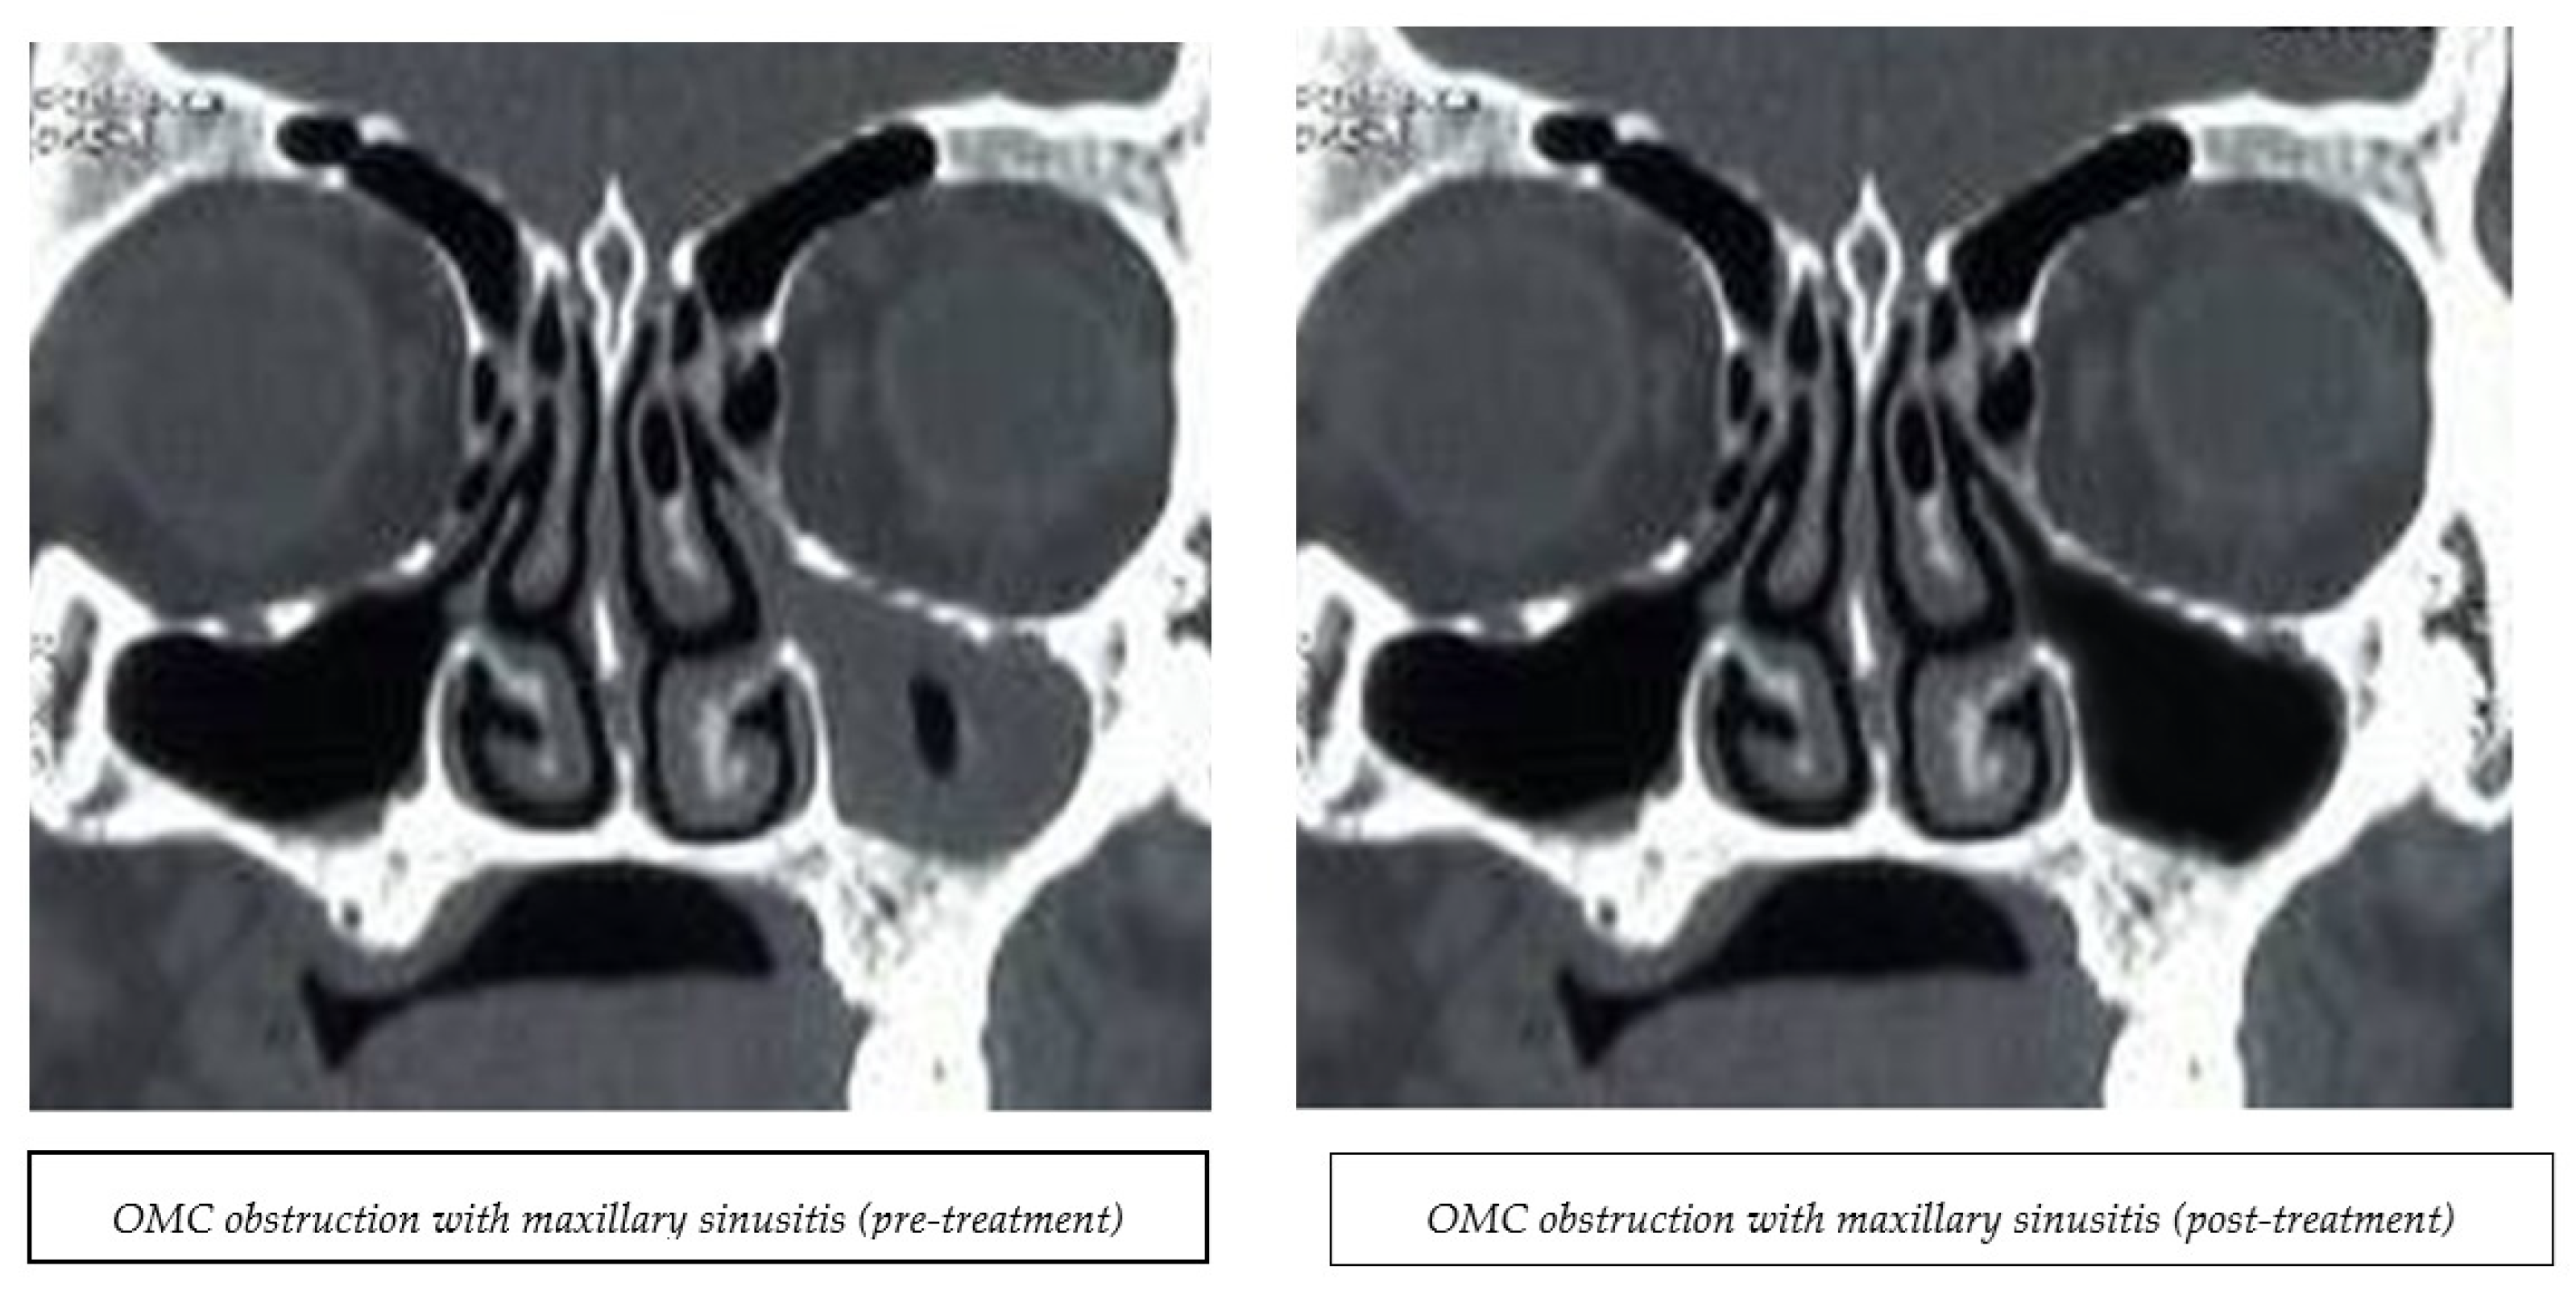

3.6. Sinus Opacification and Ostiomeatal Obstruction

| Sinus Types | Magnetic Therapy Group | Control Group | p-Value | Magnetic Therapy Group | Control Group | p-Value |

|---|---|---|---|---|---|---|

| Pre Treatment | Post Treatment | |||||

| Rt Ethmoid sinus opacification | 4 (17.4.%) | 4 (16.7%) | 0.947 | 1 (4.3%) | 4 (16.7%) | 0.157 |

| Lt Ethmoid sinus opacification | 4 (17.4%) | 3 (12.5%) | 0.681 | 1 (4.3%) | 3 (12.5%) | 0.285 |

| Rt Sphenoid sinus opacification | 3 (18.8%) | 4 (26.7%) | 0.685 | 1 (5%) | 4 (26.7%) | |

| 1 (6.2%) | 0.172 | |||||

| Lt Sphenoid sinus opacification | 2 (12.5%) | 4 (26.7%) | 0.394 | 0 (0%) | 4 (26.7%) | 0.043 |

| Rt Frontal sinus opacification | 1 (4.3%) | 1 (4.2%) | 0.975 | 0 (0%) | 1 (4.2%) | 0.243 |

| Lt Frontal sinus opacification | 1 (4.3%) | 1 (4.2%) | 0.975 | 0 (0%) | 1 (4.2%) | 0.243 |

| Rt Maxillary sinus opacification | 4(17.4%) | 5(20.8%) | 0.764 | 0 (0%) | 5 (20.8%) | 0.007 |

| Lt Maxillary sinus opacification | 5 (21.7%) | 5 (20.8%) | 0.940 | 0 (0%) | 5 (20.8%) | 0.007 |

| Rt Ostiomeatal Obstruction | 6 (26.1%) | 3 (12.5%) | 0.233 | 0 (0%) | 3 (12.5%) | 0.040 |

| Lt Ostiomeatal Obstruction | 7 (30.4%) | 4 (17.4%) | 0.297 | 0 (0%) | 4 (17.4%) | 0.015 |